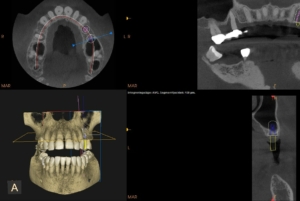

Dental tomografi (CBCT):

CBCT används för att få tredimensionella bilder, dvs en volymavbildning av käken. Den används exempelvis inför implantat/kirurgi – utredningar.

Dental tomografi (CBCT)